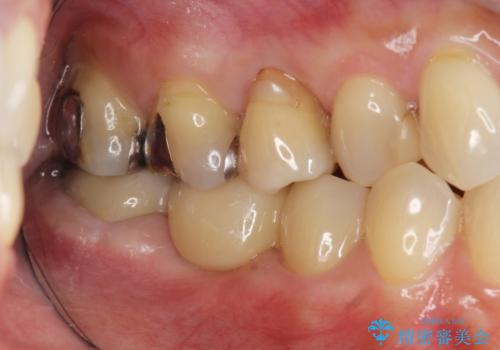

- 銀歯が取れてしまい、治療を希望され来院されました。

歯には大きな穴が開き、虫歯も大きくなってしまい残すことが難しいような状況であったため抜歯を余儀なくされました。

抜歯後はセラミックブリッジを用いた咬合機能回復を計画します。

インプラント治療に比べブリッジ治療は比較的短期に手術の必要なく終えることができます。